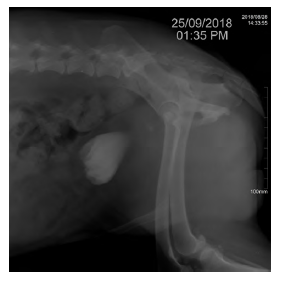

Se realiza ecografía focalizada para trauma abdominal (AFAST, por sus siglas en inglés) (Boysen y Lisciandro 2013) como prueba para el reconocimiento temprano de líquido libre en el abdomen, que en este caso arroja un resultado positivo para la presencia de líquido abdominal en las cuatro ventanas. Posteriormente, se realiza abdominocentesis con el paciente en decúbito lateral derecho para lavado y colecta de líquido peritoneal y se determina el valor de creatinina, cuyo resultado es de 8 mg/dl. Se lleva a cabo un lavado peritoneal con cloruro de sodio 0,9% con el fin de estabilizar al paciente y luego se procede a realizar una radiografía simple (figura 1), una uretrocistografía retrograda (figura 2) con medio de contraste positivo, en este caso iopramida (Ultravist®), en la cual se observa la disrupción uretral y zonas radiopacas en abdomen compatibles con la presencia de medio de contraste en el abdomen caudal, cuyo resultado es positivo para ruptura uretral. Se toman muestras de sangre para cuadro hemático y química sanguínea (ALT, creatinina, potasio, albúmina, calcio) en el que se observan como anormalidades el aumento de creatinina en valores de 2,5 mg/dL y anemia normocítica hipocrómica. No fueron autorizadas la totalidad de los exámenes solicitados. Se realiza un electrocardiograma en el cual no se encuentran anormalidades. Se sugiere la realización de laparotomía exploratoria para verificar daños adyacentes y ubicar y reparar el sitio exacto donde se produjo el rompimiento del tracto urinario inferior.

Uretrografia de contraste positivo retrógrada con iopramida (Ultravist®). En la imagen se observa la presencia del medio de contraste en la porción caudal del abdomen, lo que indica ruptura de vías urinarias inferiores.

FIGURA 2: Uretrografia de contraste positivo retrógrada con iopramida (Ultravist®). En la imagen se observa la presencia del medio de contraste en la porción caudal del abdomen, lo que indica ruptura de vías urinarias inferiores.

Fuente: elaboración propia.